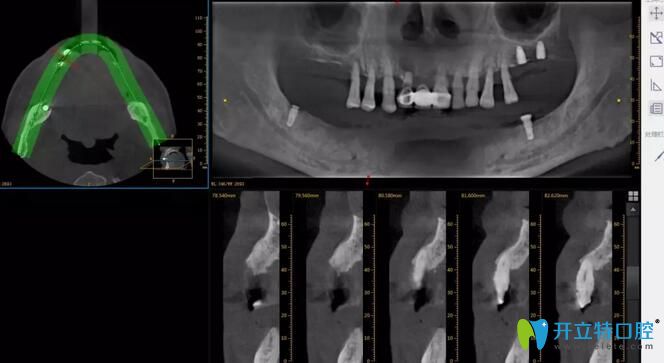

1、種植牙案例

牙齒問題:單顆牙缺失

治療方案:德國瑞西歐 即刻種植

患者點評:牙齒掉了非常影響美觀,想做種植牙,不知道深圳哪個好?朋友給推薦了深圳諾德口腔,確實不錯,剛種植完就能吃東西了,而且正好趕上活動,進口種植牙才花了不到7000元,和我之前在其他口腔咨詢的價格相比,還是非常便宜的。

深圳諾德口腔單顆牙缺失治療前后照片